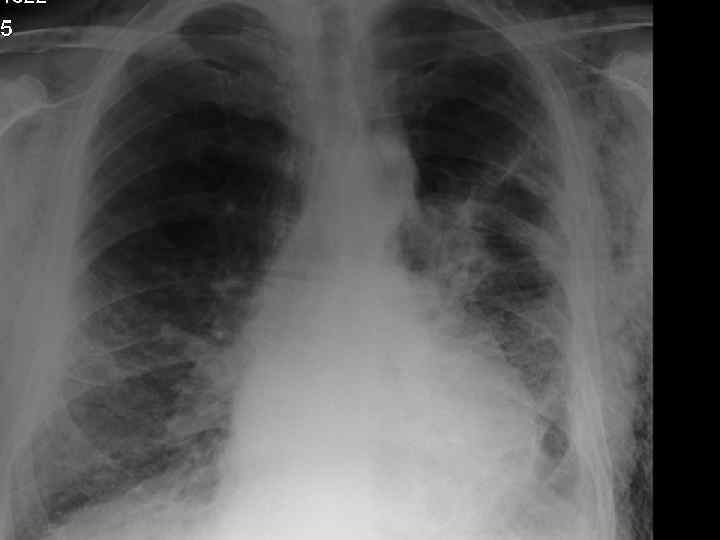

History n Mr X is a 74 year old Caucasian male n PC: Acute SOB n HPC: SOB episode began at 10 -11 am this morning gradually worsening, but suddenly became acutely worse. Noticed by neighbour. Ambulance blue lighted to AE resus

Examination n n n Anxious, gasping for breath, holding arms on trolley, Abdominal muscles used for breathing Central cyanosis Pulse 106 bmp regular HS I + II + 0 Apex beat laterally displaced Pitting right ankle oedema No sacral oedema

Respiratory R n n n L Resp rate 22 pm Trachea central Uneven lung expansion Hyperinflated upper chest Hyperresonant percussion Exp wheezing Insp crackles

Impressions n Pneumothorax n COPD/Fibrosing alveolitis n AHA n Congestive heart failure n Newly diagnosed Diabetes mellitus

Investigations. n CXR n CT n Arterial blood gases

Clinical features n Progressive breathlessness n Cyanosis n Pulmonary hypertension/cor pulmonale n Clubbing n Bilateral fine end insp. Crackles n X-ray shows ground glass appearance

Investigations n Chest X-ray n High res. CT scan n Respiratory function tests n Blood gasses n ANF, RF, ESR n Bronchoalveolar lavage n Biopsy